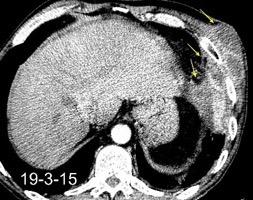

Marzo 2014: Perforación longitudinal distal secundaria a episodio de vómito (síndrome de Boerhaave). Derrame pleural izdo. que evoluciona a empiema.

Wang C-T et al. Tension hydropneumothorax in a Boerhaave syndrome patient: A case report . World J Emerg Med, 2021. Katabathina V et al. Nonvascular, nontraumatic mediastinal emergencies in adults:a comprehensive review of imaging findings. Radiographics. 2011.